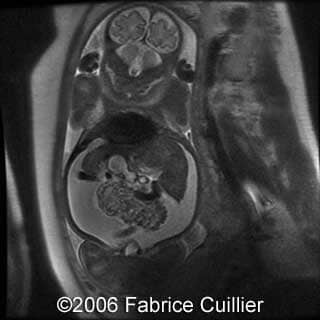

MRI images

- Bilateral kidney’s enlargement without increased echogenicity. The corticomedullary differentiation seemed normal

At 37 week of pregnancy, a cesarean section was performed. Female baby was born weighting 5.1 kg wit the Apgar scores 1/1/1. The baby was referred to intensive care unit. The newborn’s abdomen was distended due to bilateral kidney’s enlargement. Postnatal scans confirmed prenatal findings of bilateral kidney’s enlargement. Renal and hepatic functions were abnormal. A puncture of the ascites was performed (>0.5 l), but anuria appeared after that. Despite of intensive neonatal care, the baby died on the first postnatal day due to circulatory collapse and respiratory distress. Parents refused the postmortem examination, but the kidney biopsy was done with the diagnosis of nephroblastomatosis.

Our final diagnosis was Perlman syndrome.